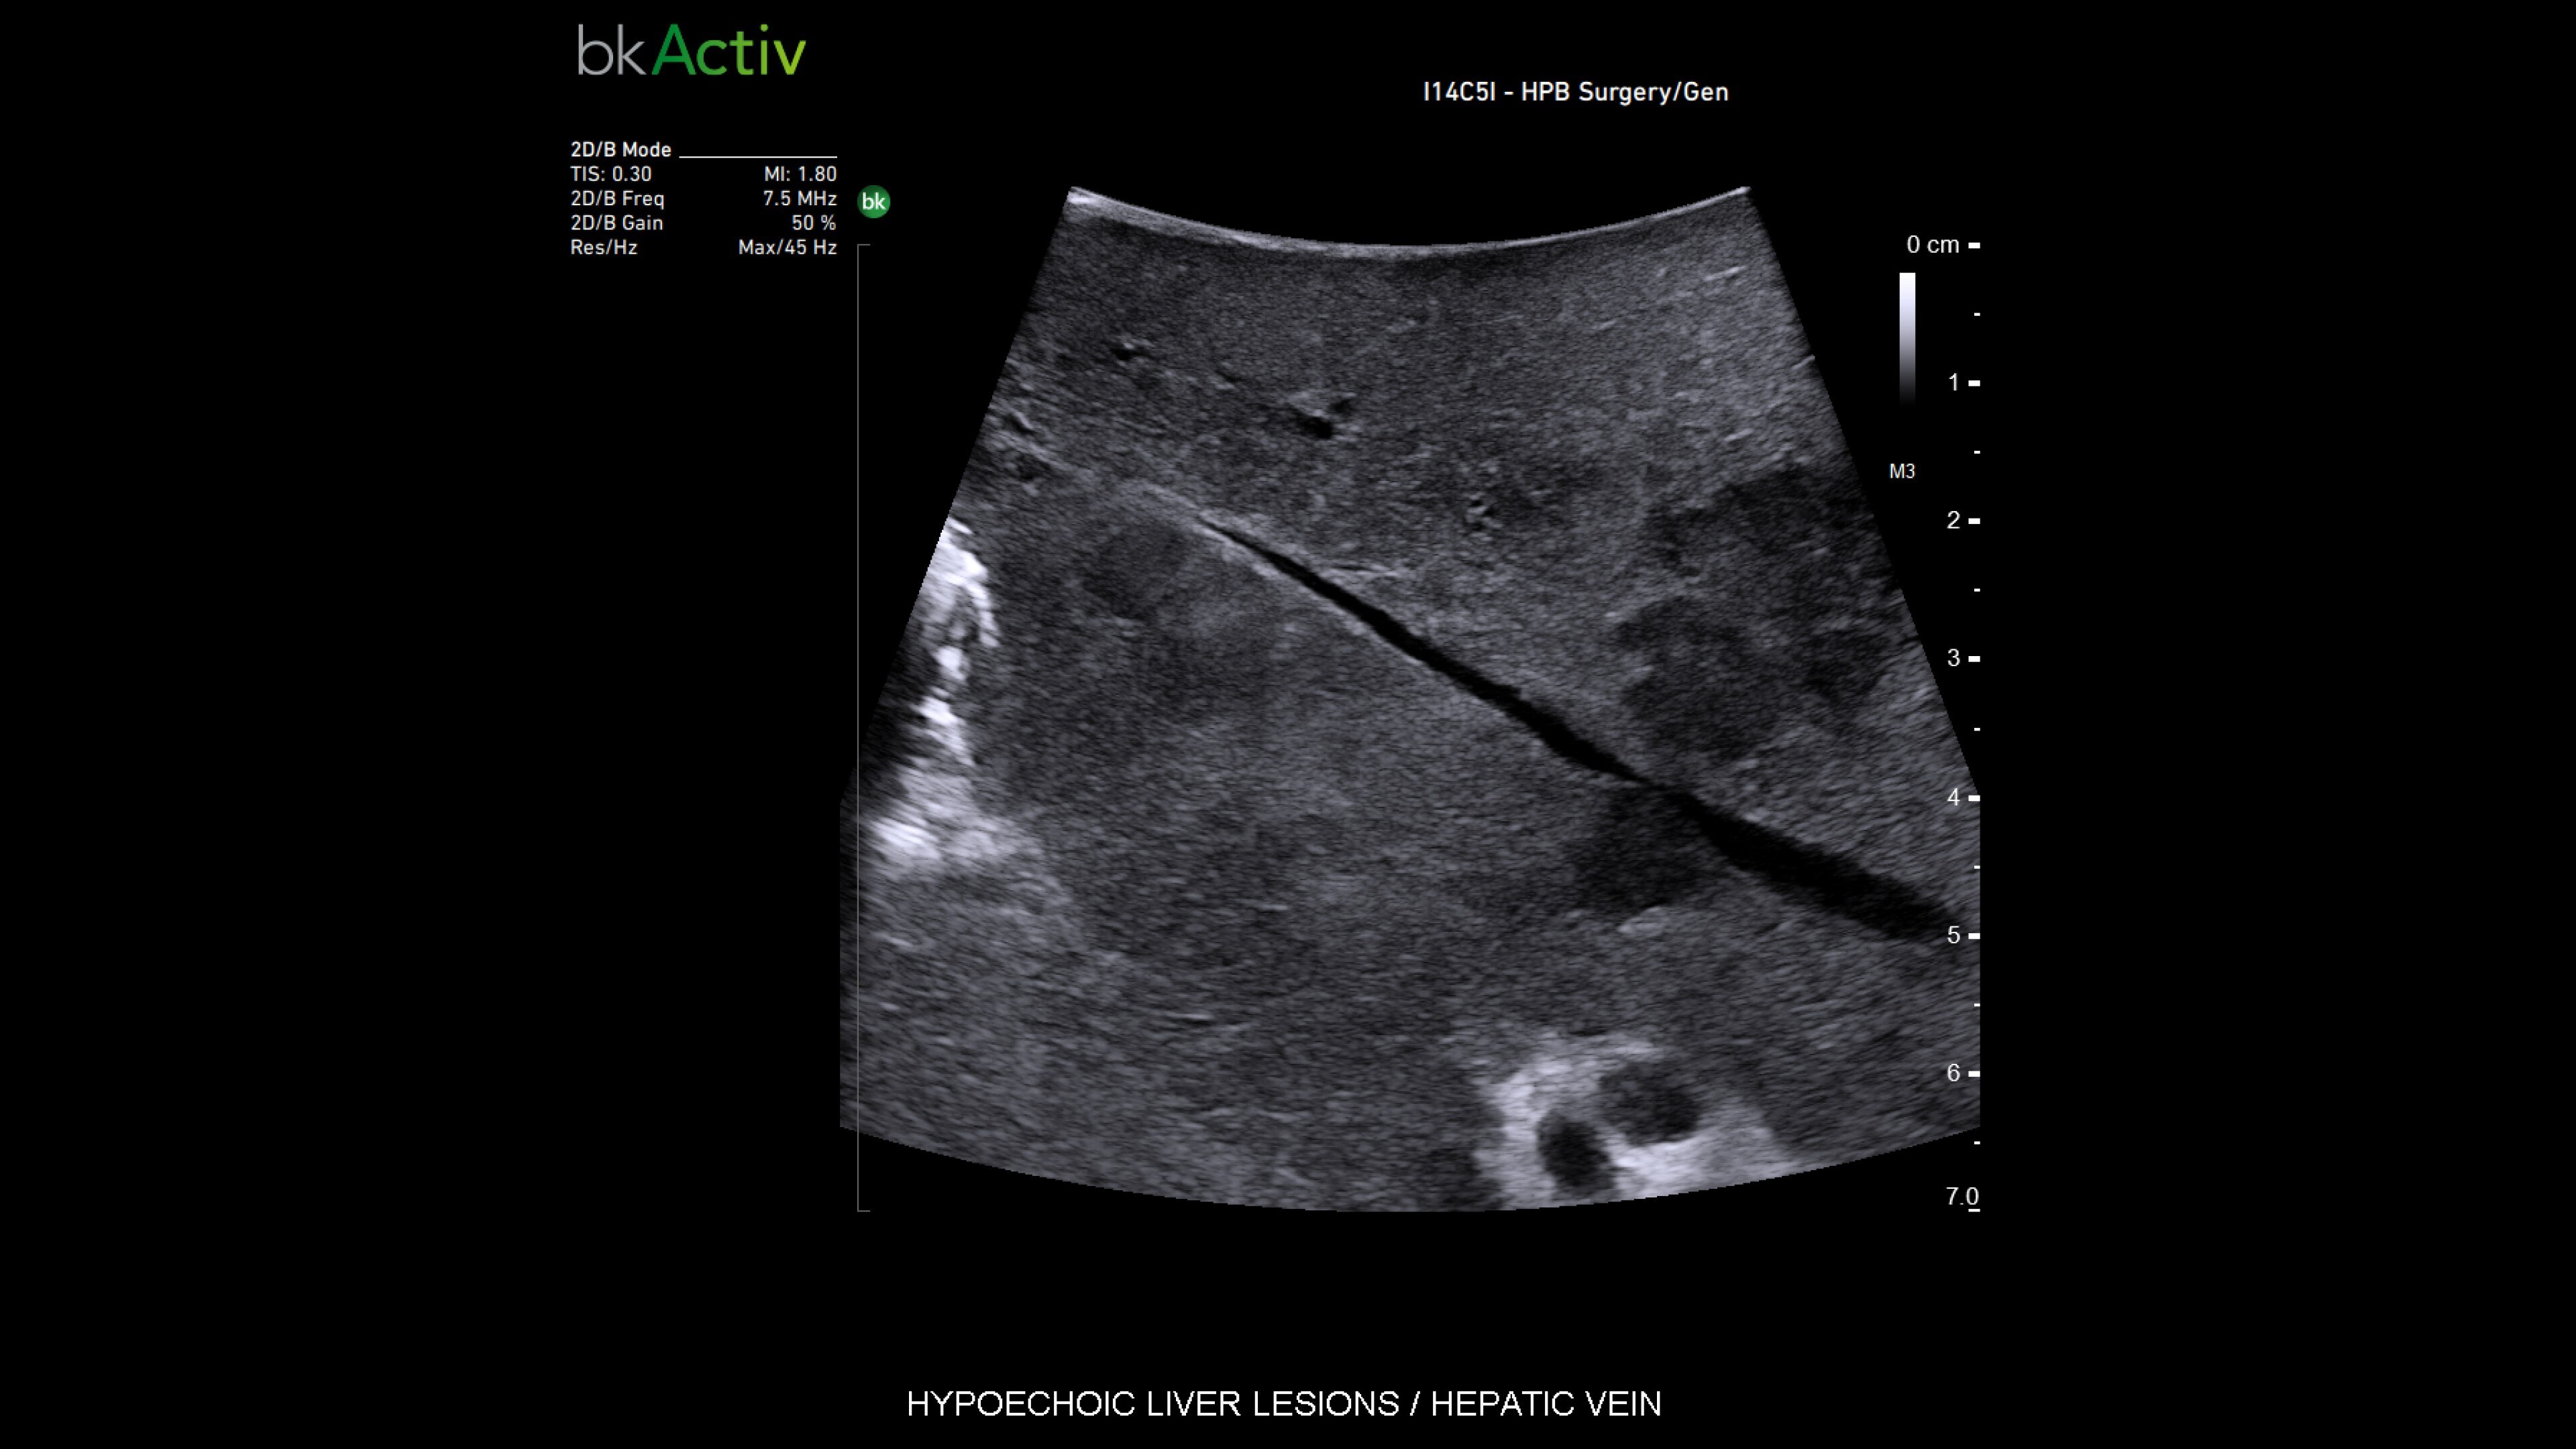

Resection ultrasound

Active imaging supports liver and pancreas tumor resection procedures by helping you visualize complex anatomical variations and relationships to vascular structures, identify tumor location, define adequate margins of resection, and assess surgical planning.

Active imaging with intraoperative ultrasound supports critical decision-making in open or minimally invasive tumor resections.

• Visualize complex anatomical variations.

• Identify tumor location, proximity, and invasion of vasculature.

• Define adequate margins of resection.

• Understand relationship to vascular structures.

• Assess surgical planning and check for vessel patency at the end of the procedure.

Use of ultrasound during complex redo open liver resection.